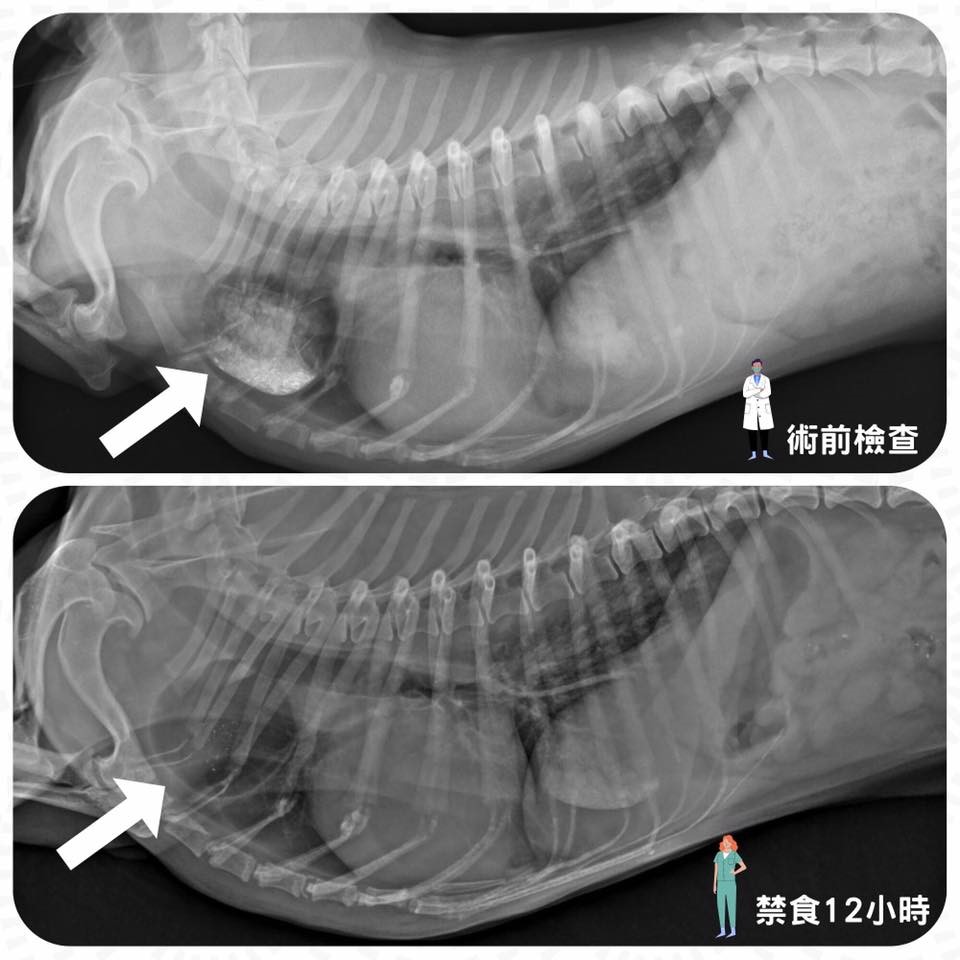

*附圖為一隻術前檢查意外發現有食道憩室的臘腸,為了避免麻醉後的返流風險,特地延長禁食時間達12小時,在禁食12小時候,可見箭頭處的食物都不見了!由此可知,術前檢查跟正確的禁食時間就可以幫我們避免掉很大的麻醉風險喔!